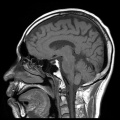

2016年06月01日:頭部MRI(ほぼ)異常無し

頭部MRI検査の結果が届いた。所見は、ほぼ全項目問題なしなのだが、唯一「脳出血」の項に、「大きさが数ミリ程度の小さな脳出血(微小脳出血)のアトがあります。あまり神経質になる必要はありませんが、油断してもいけません。高血圧や糖尿病などの持病がある場合はしっかりとなおしましょう」..いつの間に [;_ _]。まぁ、ここらあたりが私の死因になるのかなぁ..(血筋だしなぁ..)

もちろん、写真をお見せする。キモいグロい見たくないと言われても、掲載する [^J^]。エンタメ視点から、できるだけ見応えのあるモノを選んだので、ご堪能ください。[^.^](こういうの、遺影に使ったら、顰蹙ものかしら? [;^J^])